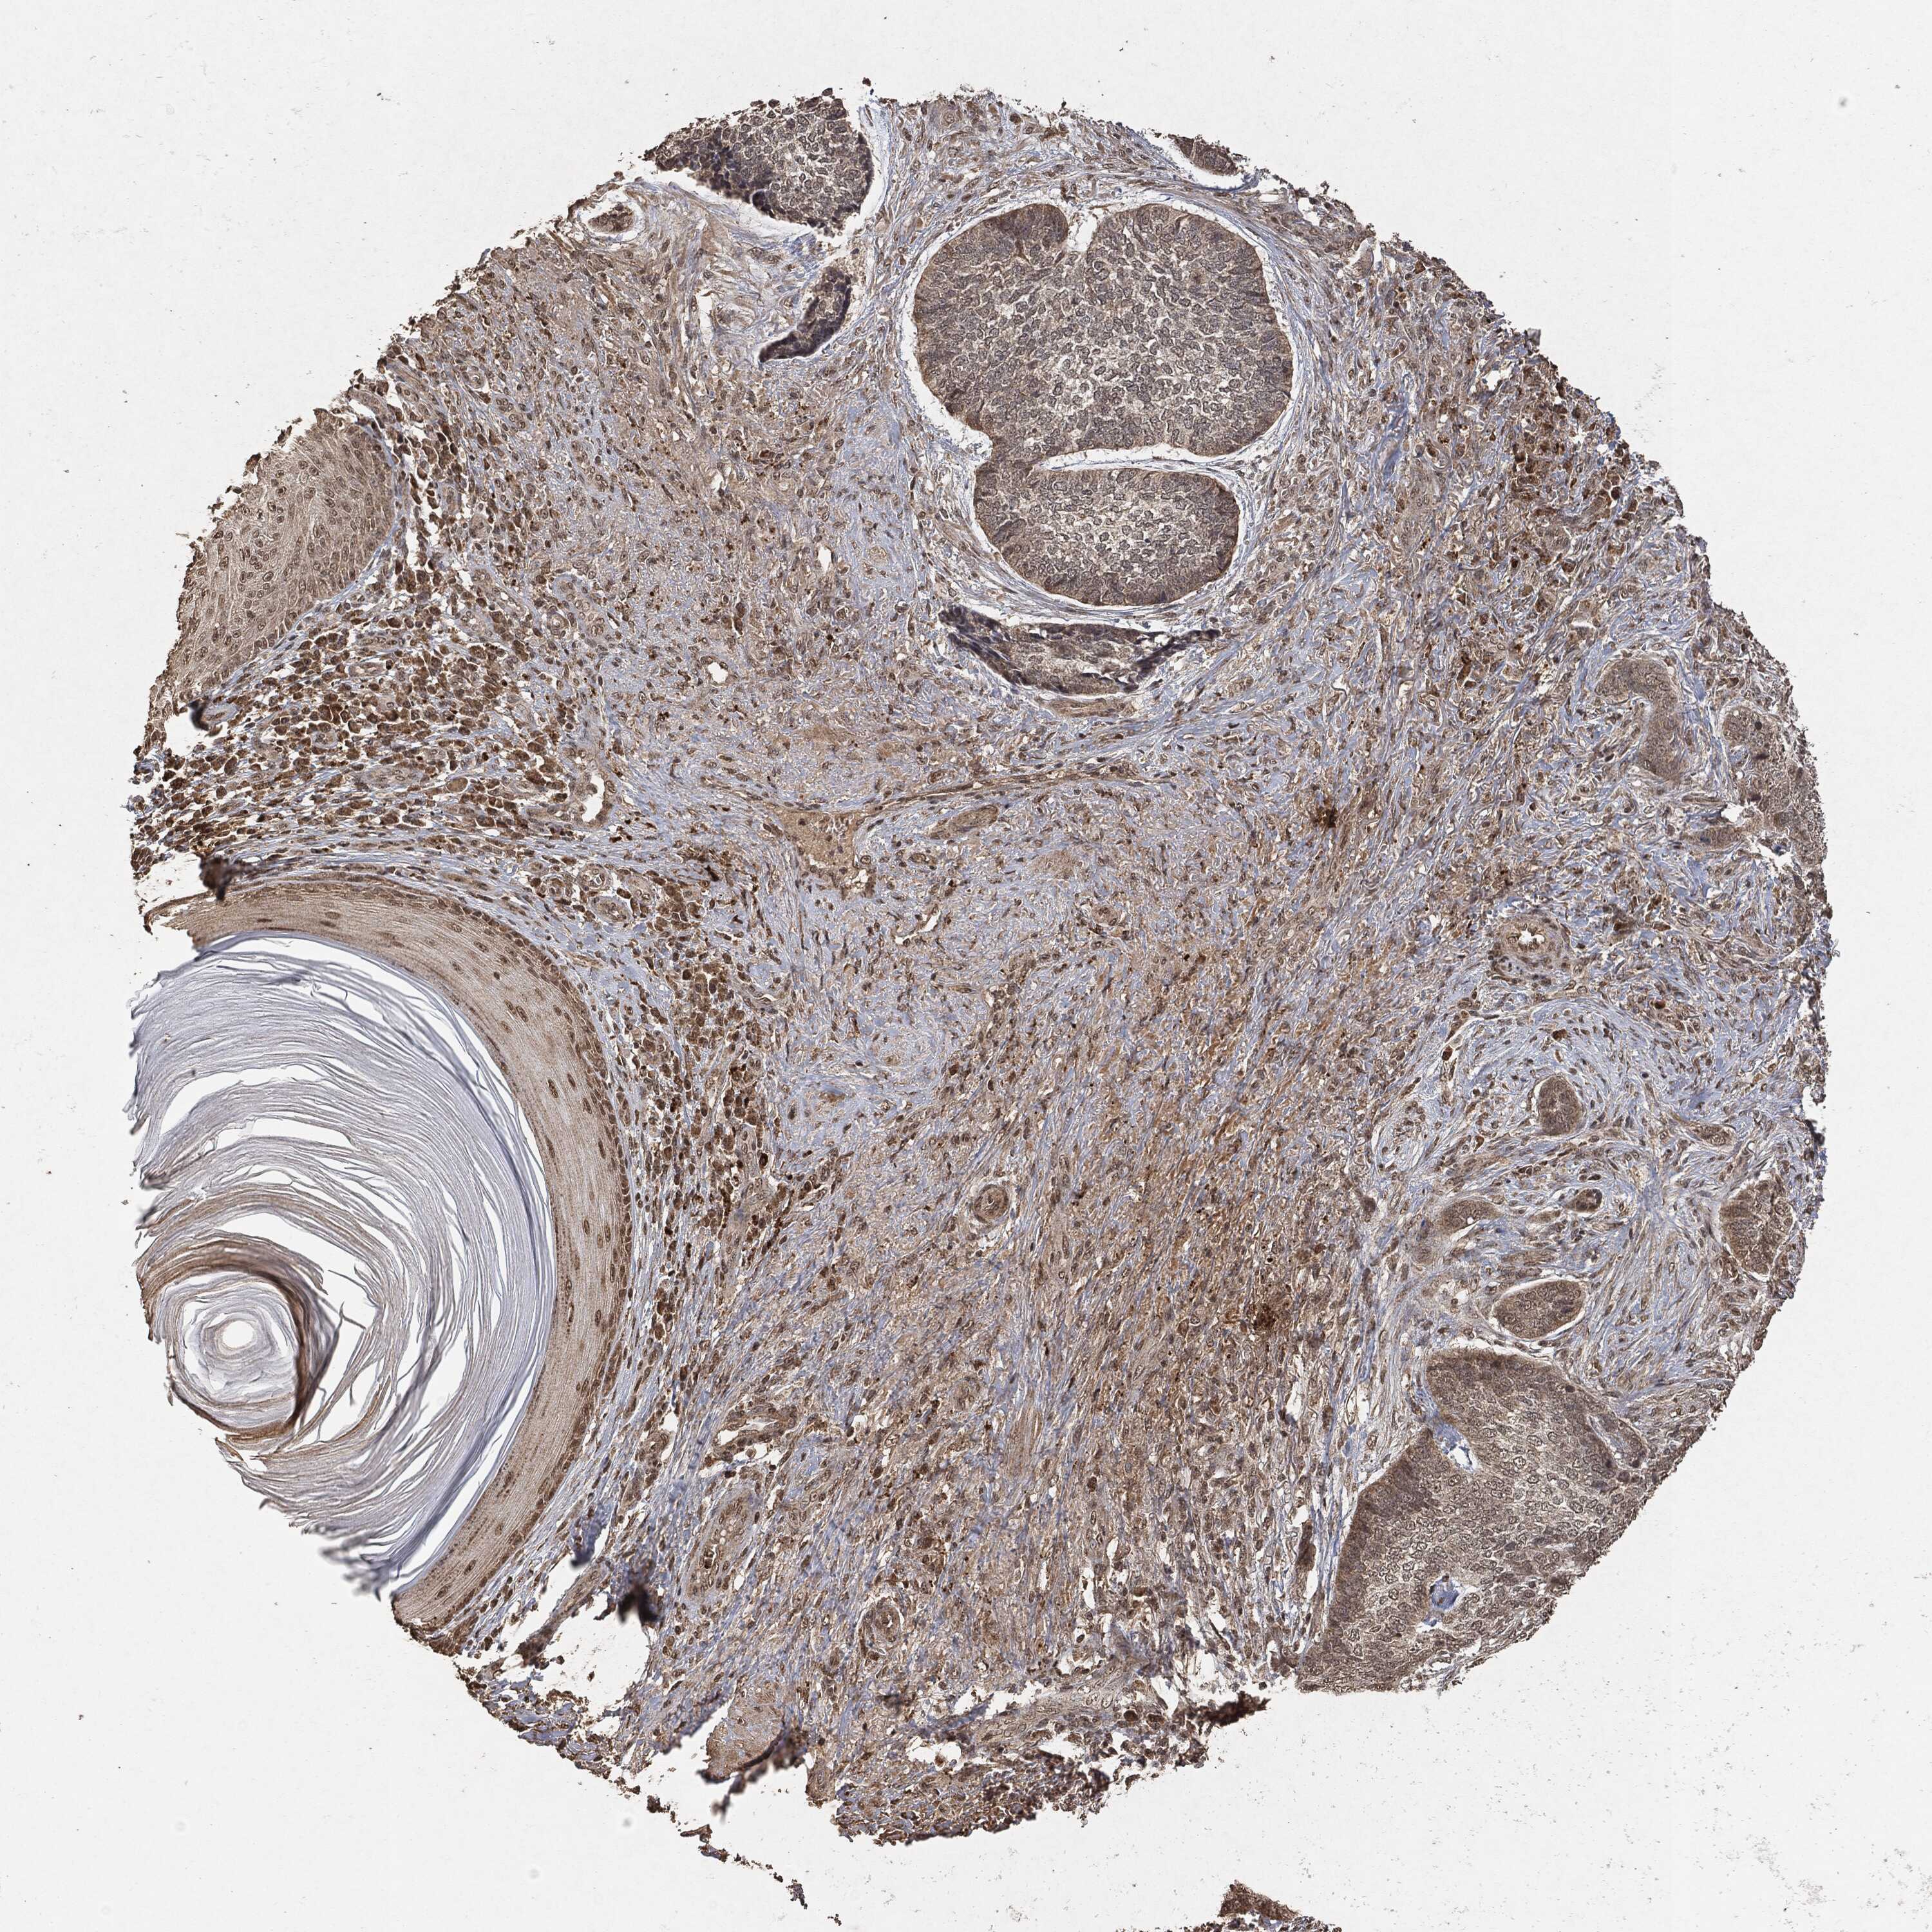

SKIN CANCER - Protein expressioni

A mouse-over function shows sample information and annotation data. Click on an image to view it in a full screen mode. Samples can be filtered based on level of antibody staining by selecting one or several of the following categories: high, medium, low and not detected. The assay and annotation is described here.

Antibody stainingi

Antibody staining in the annotated cell types in the current human tissue is reported as not detected, low, medium, or high, based on conventional immunohistochemistry profiling in selected tissues. This score is based on the combination of the staining intensity and fraction of stained cells.

Each image is clickable and will lead to virtual microscopy that enables deeper exploration of all samples and also displays staining intensity scores, fraction scores and subcellular localization as well as patient and tissue information for each sample.

CAB000035

Staining

High

Medium

Low

Not detected

Squamous cell carcinoma in situ, NOS